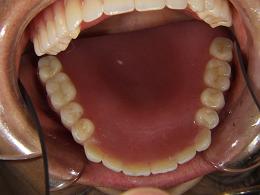

上の総入れ歯

口腔内の状態です!